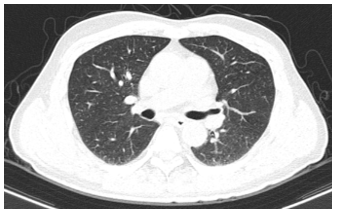

- Chụp cắt lớp vi tính ngực:

Hình 2: Hình ảnh chụp cắt lớp vi tính lồng ngực: Không thấy các tổn thương thứ phát